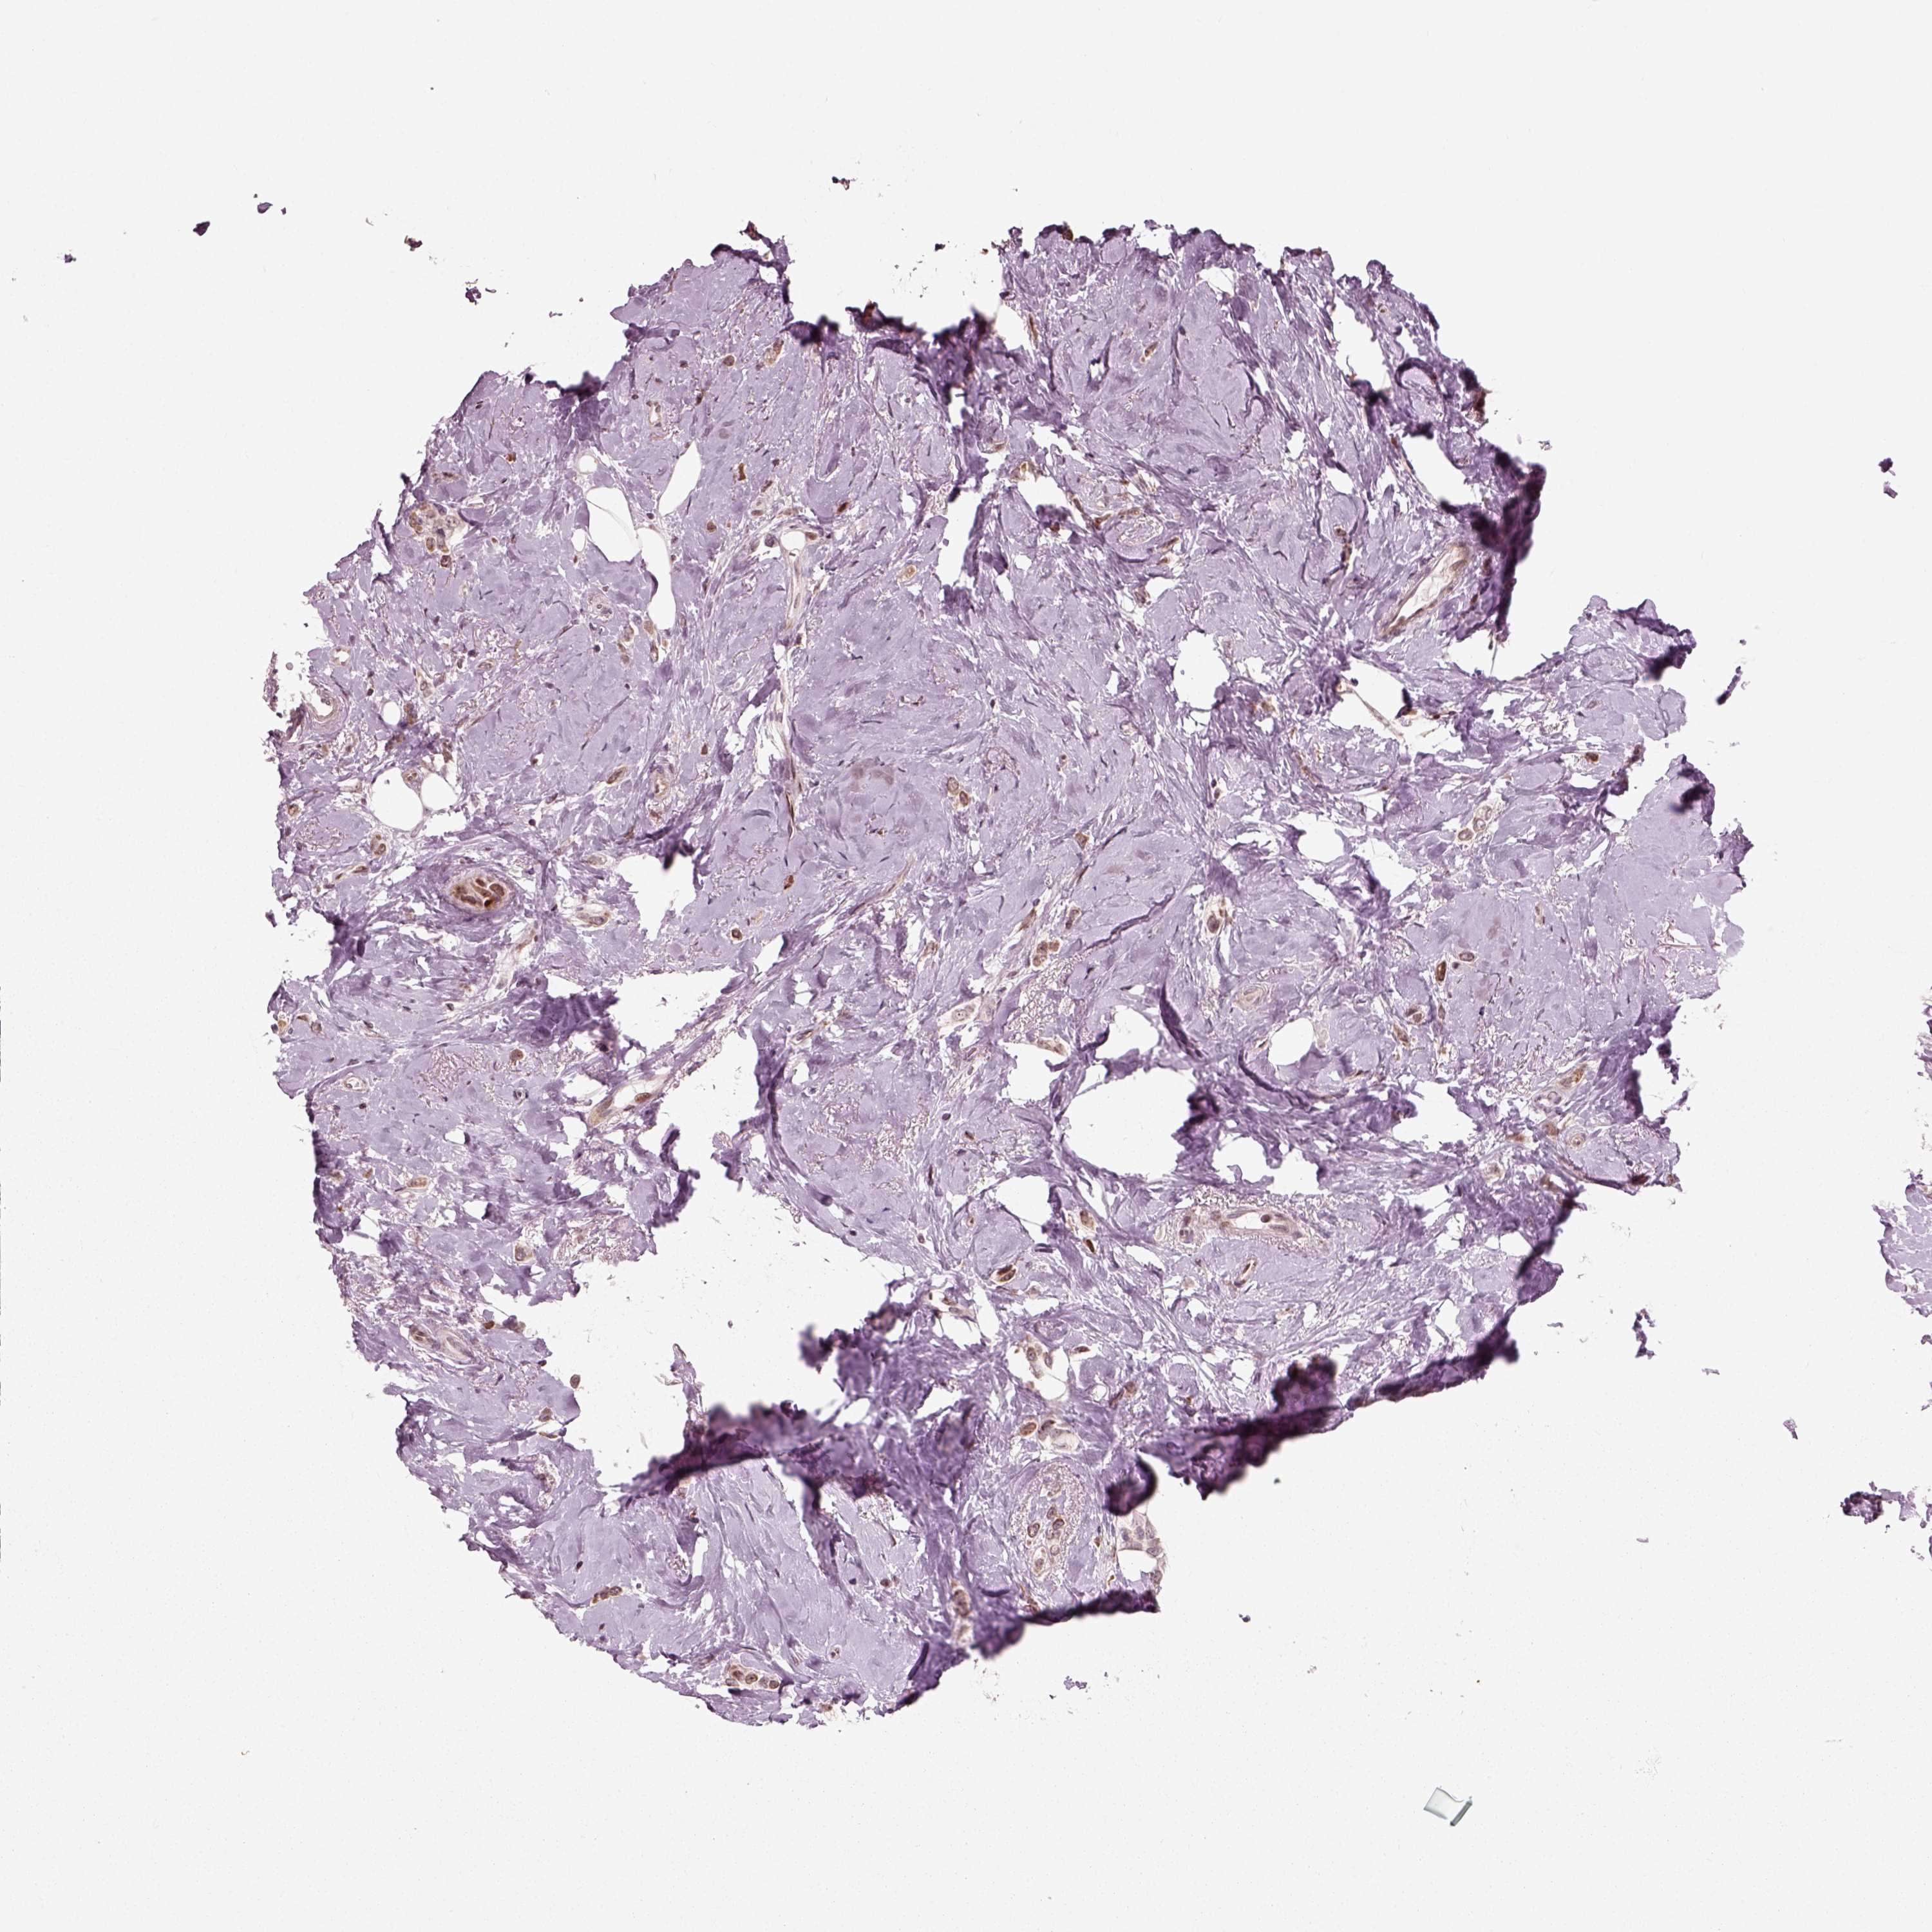

CANCER BREAST CANCER Show tissue menu

BRCA TCGA BRCA VALIDATION PROTEIN EXPRESSION

Breast cancer

Human cancer

Breast invasive carcinoma

CDC14A is not prognostic in Breast Invasive Carcinoma (TCGA)